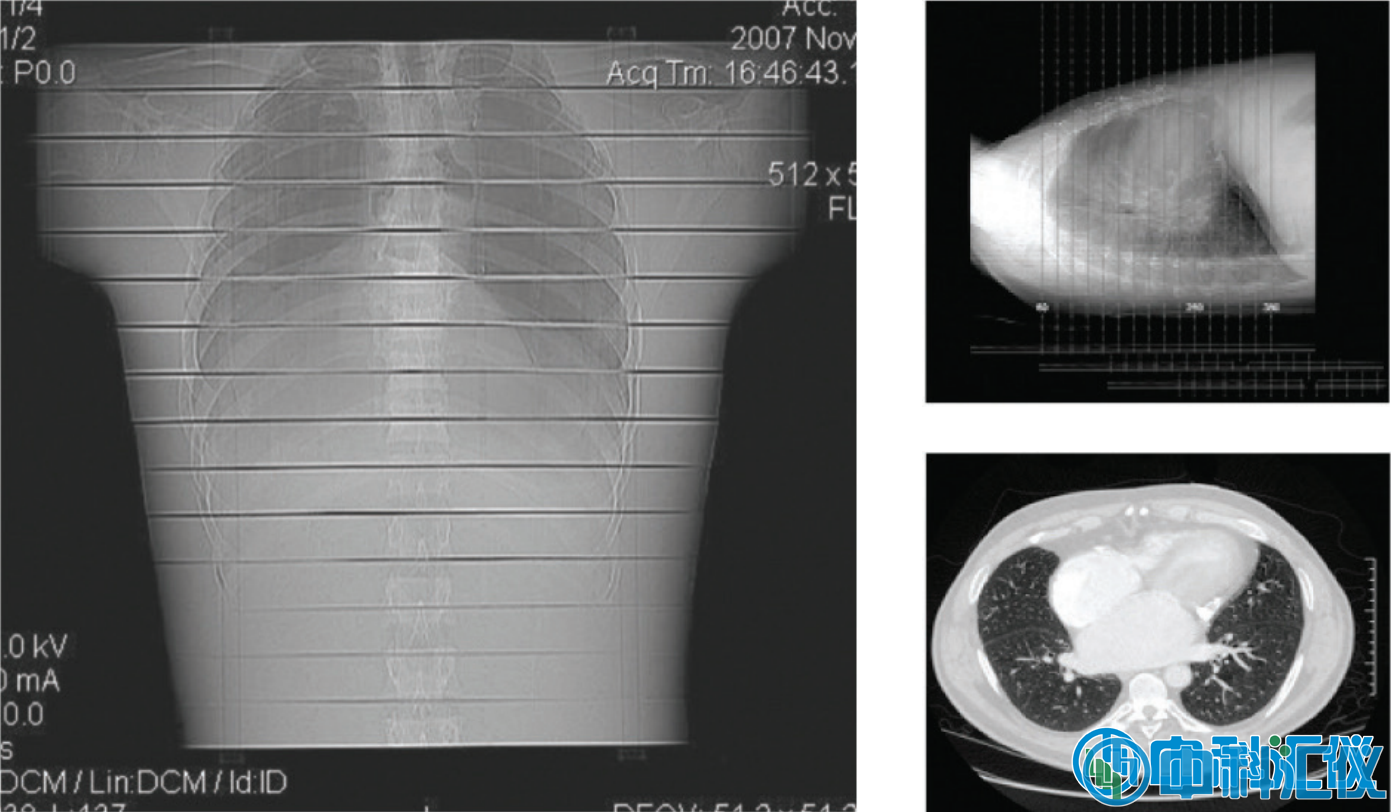

胸部模型劑量測定應(yīng)用

典型的胸部輻射分析。結(jié)果取自一項(xiàng)體內(nèi)研究,該研究使用 CT 掃描儀對胸部進(jìn)行 64 層切片檢查。

實(shí)際結(jié)果顯示了典型模型曝光下 Gafchromic? LD-V1 膠片的一條條帶。